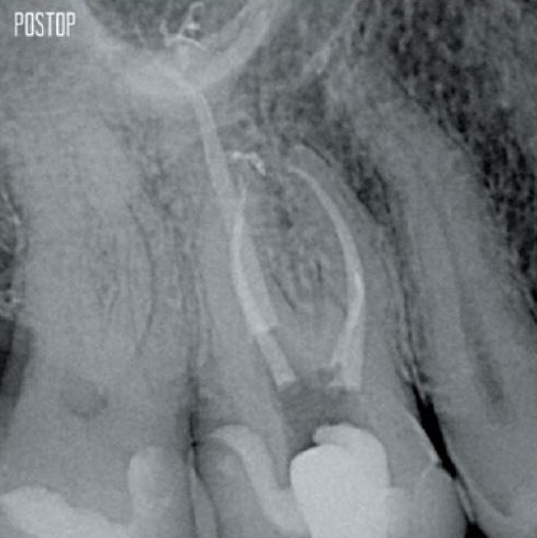

Photos avec l’aimable autorisation du Dr Ahmed Salman